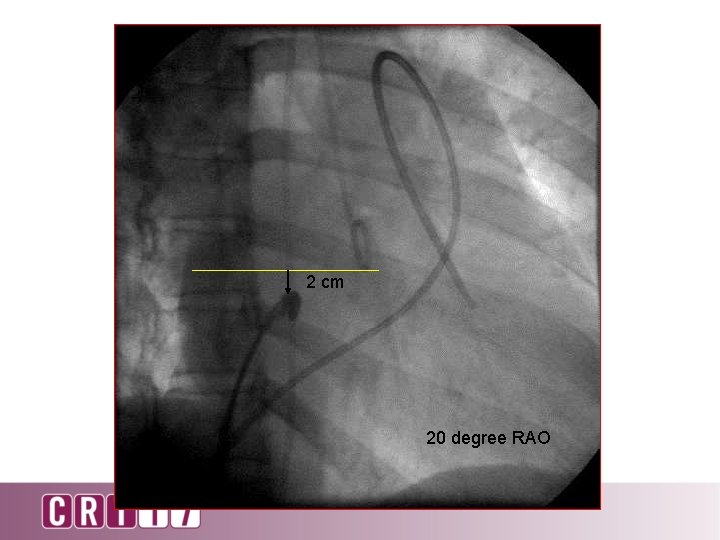

2 cm 20 degree RAO